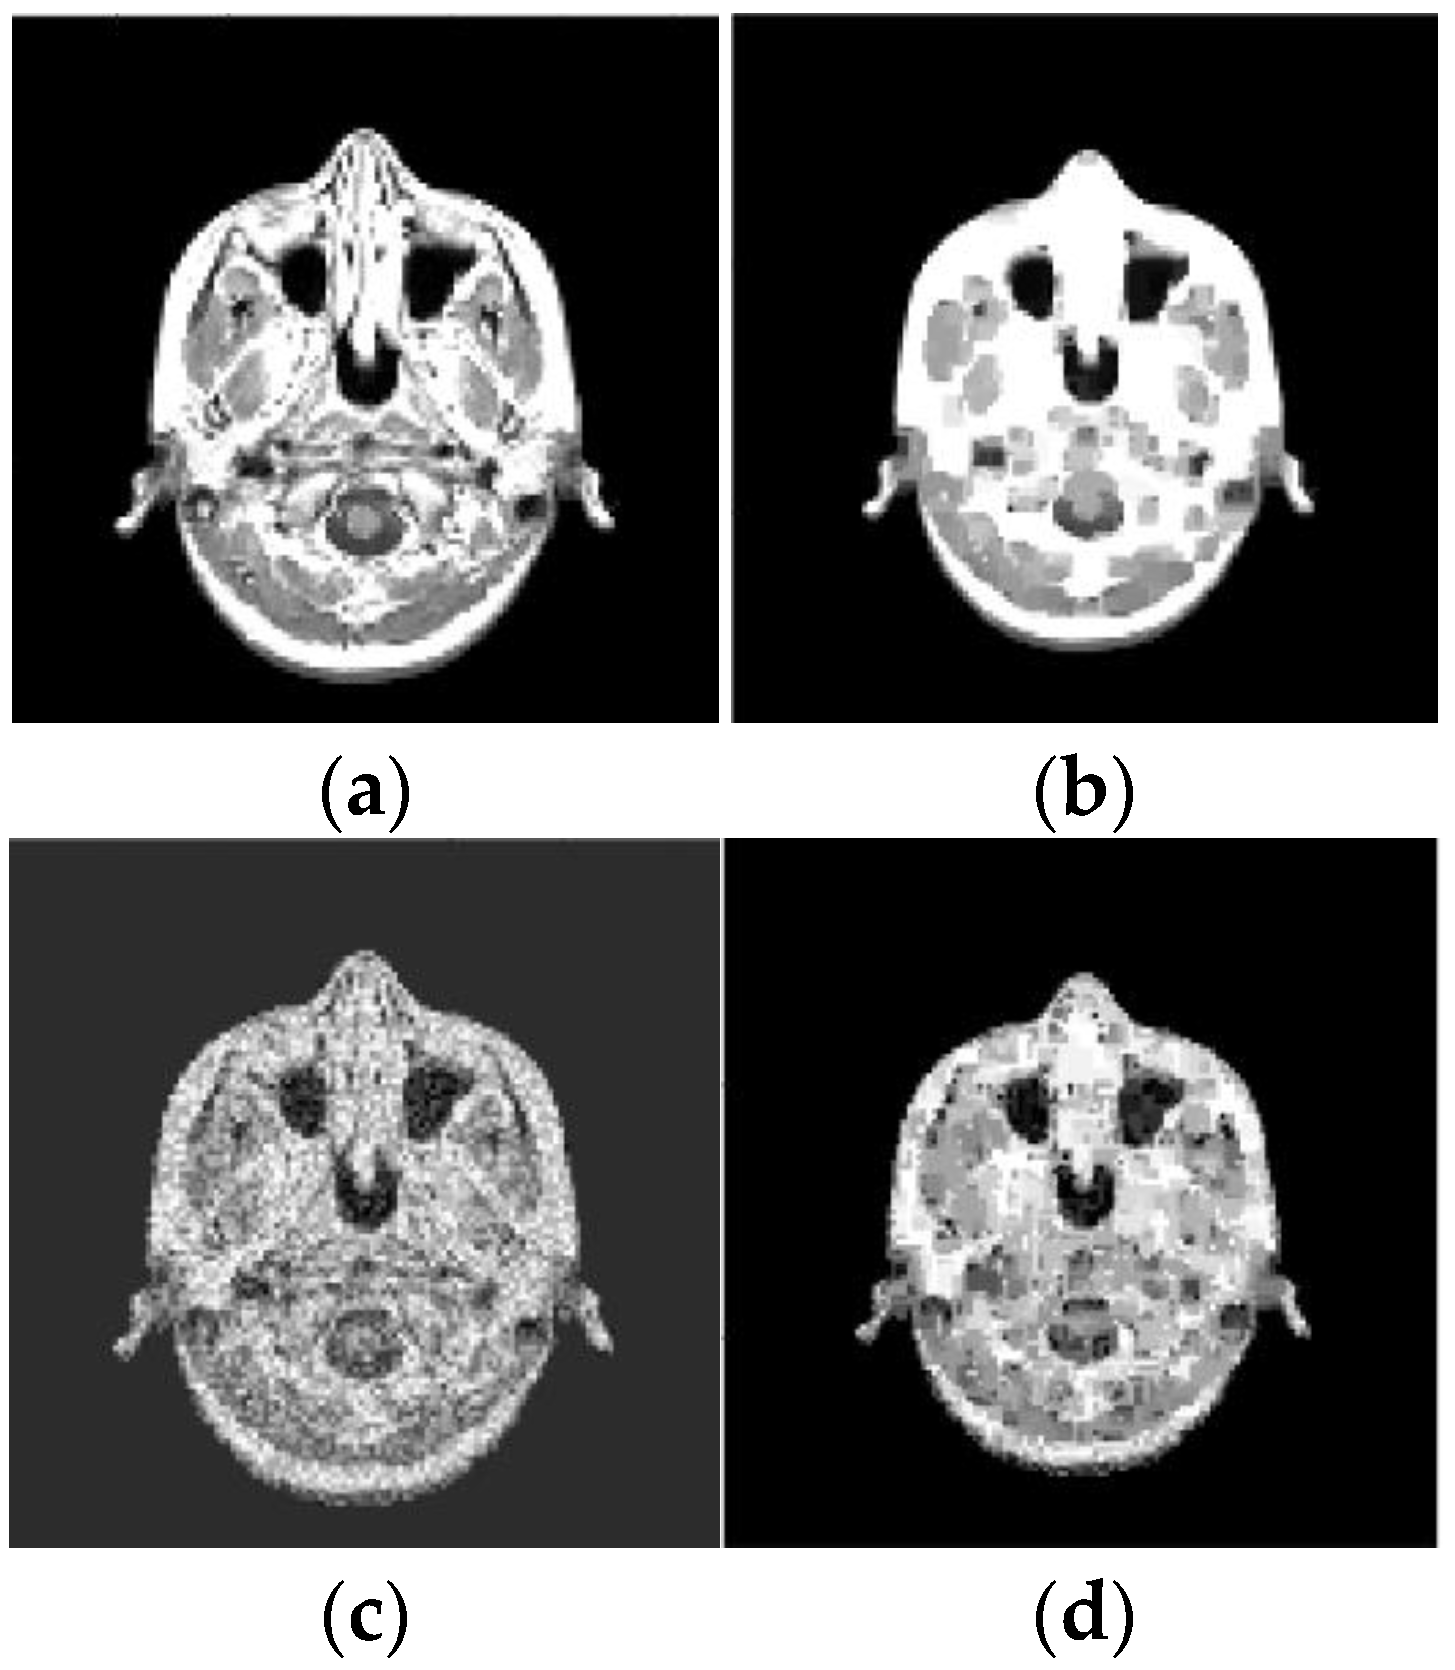

4.3. Inverse Radon Image Reconstruction